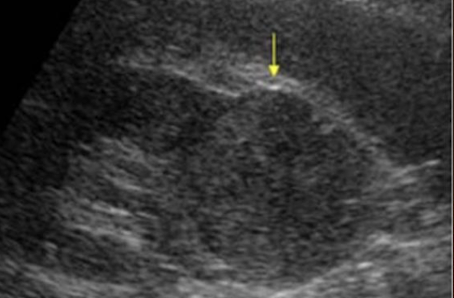

complex mass

shows characteristics of both cystic and solid lesions

may contain septations, thick walls > 1 mm, nodularity, calcifications, internal echoes from areas of necrosis, hemorrhage, or abscess/infection

** if there is septation in cyst, put color box on it, especially if its thick

describe

“complex structure measuring 3 cm x 3 cm x 3 cm noted in UP/MP LK. vascularity noted within”

complex cyst

may contain septations, thick walls, calcifications, internal echoes, and mural nodularity

considered malignant until proven benign, especially if septa >1 mm thick with vascular flow on color or Power Doppler

any irregularity at the base of the cyst should be considered a malignant growth

??

has septations and solid components